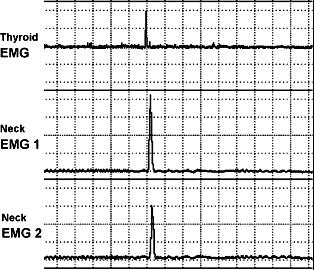

实验中根据需要动态连续监测ECoG和食道平滑肌肌电图。手术中在胎羊颈部由上而下在甲状腺部位及食道平滑肌上埋设的三对电极可以记录食道平滑肌的肌电图(electromyography,EMG),EMG电活动的出现从上至下有时间上的先后关系(图2-4)。胎儿的ECoG可以分为高电压(high-voltage,HV)低频和低电压(low-voltage,LV)高频时相。大约有5%左右的区域既不属于HV,也不属于LV,被认为是中间ECoG活动。发生在HV和LV时相的吞咽活动,用此时相的吞咽总个数除以其时间段,以每分钟LV或HV的吞咽个数表示。

图2-4 食管平滑肌肌电图反映的胎羊吞咽活动

图中上、中、下三条曲线分别代表胎羊颈部由上至下(甲状腺部位、颈部食道平滑肌的上和下)埋设的三对电极记录到的食道平滑肌的EMG,EMG电活动的出现从上至下有时间上的先后关系。